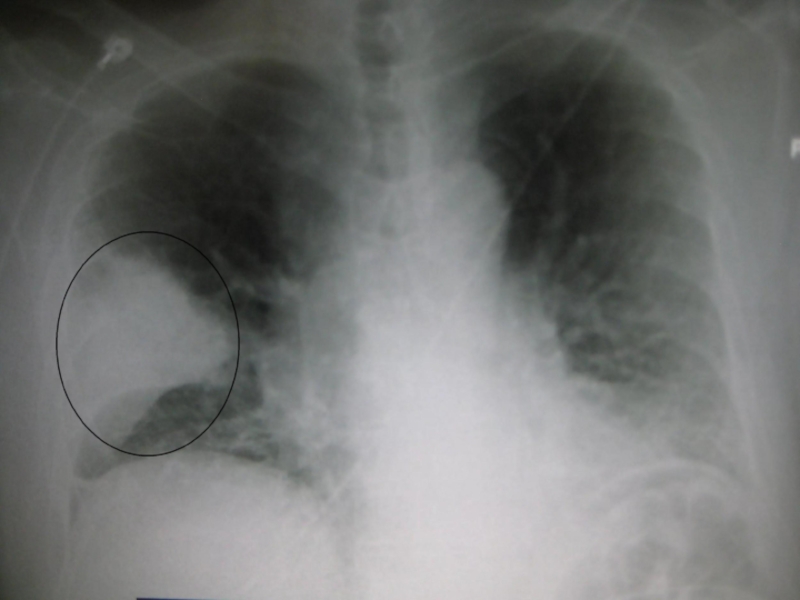

Слайд 52Абсцедирующая пневмония

Абсцесс выглядит как кольцевидная тень с уровнем жидкости.

Абсцедирующая пневмонияАбсцесс выглядит как кольцевидная тень с уровнем жидкости.

Слайд 60Очаговая бронхопневмония (уплотнение легочного рисунка в прикорневой зоне в нижней доле

правого легкого)

Очаговая бронхопневмония (уплотнение легочного рисунка в прикорневой зоне в нижней доле правого легкого)